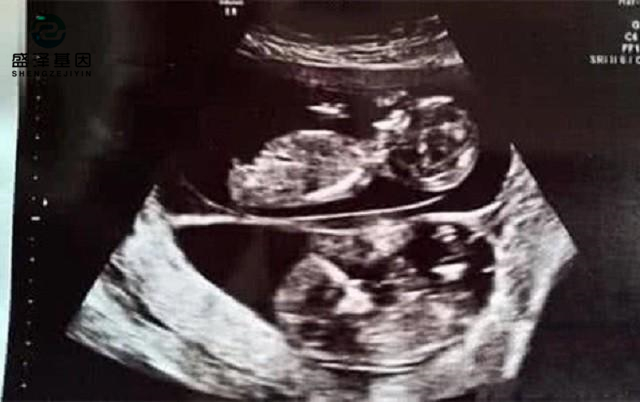

當(dāng)妻子的肚子漸漸大了,阿杰帶妻子去做B超的時候,得到了一個更加令他欣喜若狂的消息:妻子懷的是雙胞胎!

不過,有些雙胞胎確實(shí)會長得不一樣。因?yàn)殡p胞胎的淺層含義,就是一胎有兩個胎兒。通常情況會分同卵雙胞胎和異卵雙胞胎。

同卵雙胞胎就是一個受精卵分化成兩個胎兒,所以他們的長相幾乎一模一樣,只是會有細(xì)微的、不易察覺的區(qū)別。

而異卵雙胞胎則是母親的兩個卵子同時和父親的兩個精子結(jié)合成受精卵。同一胎會有不同長相、不同性別的顯著性狀出現(xiàn)。

前言曾提,異卵雙胞胎是女性的兩個卵子和男性的兩個精子結(jié)合。但是通常女性一個月只會排一次卵,只有少數(shù)女性排兩個卵子。

一般情況下,兩顆卵子不會同時排出,而且通常存活時間不短,大概24~48小時,也就是一到兩天。

在存活時間中,頭15~18個小時的受精能力是最強(qiáng)的。同時,男性的精子在女性體內(nèi)能存活的時間更長,有2~3天。

也就是說,阿杰的妻子在2天時間內(nèi),同時和不同的男性同房,在一顆卵子成為受精卵之后,另一顆卵子又受精了。

這種兩顆卵子在同一個排卵期先后受精的行為,在醫(yī)學(xué)上又稱作同期復(fù)孕。其實(shí)還有另外一種更為復(fù)雜的情況,叫做異期復(fù)孕。

異期復(fù)孕的意思是,一名女性在上一個排卵期已經(jīng)受孕,但是在下一個排卵期依然排卵,并且和男性發(fā)生關(guān)系,再次受孕。

但是異期復(fù)孕的幾率也非常低,眾所周知,女性在懷孕后,是大概率不會排卵的。孕期排卵是非常少的情況。

從概率上來說,阿杰的妻子這種情況可以稱得上是“百萬里挑一”了,甚至是“千萬里挑一”。